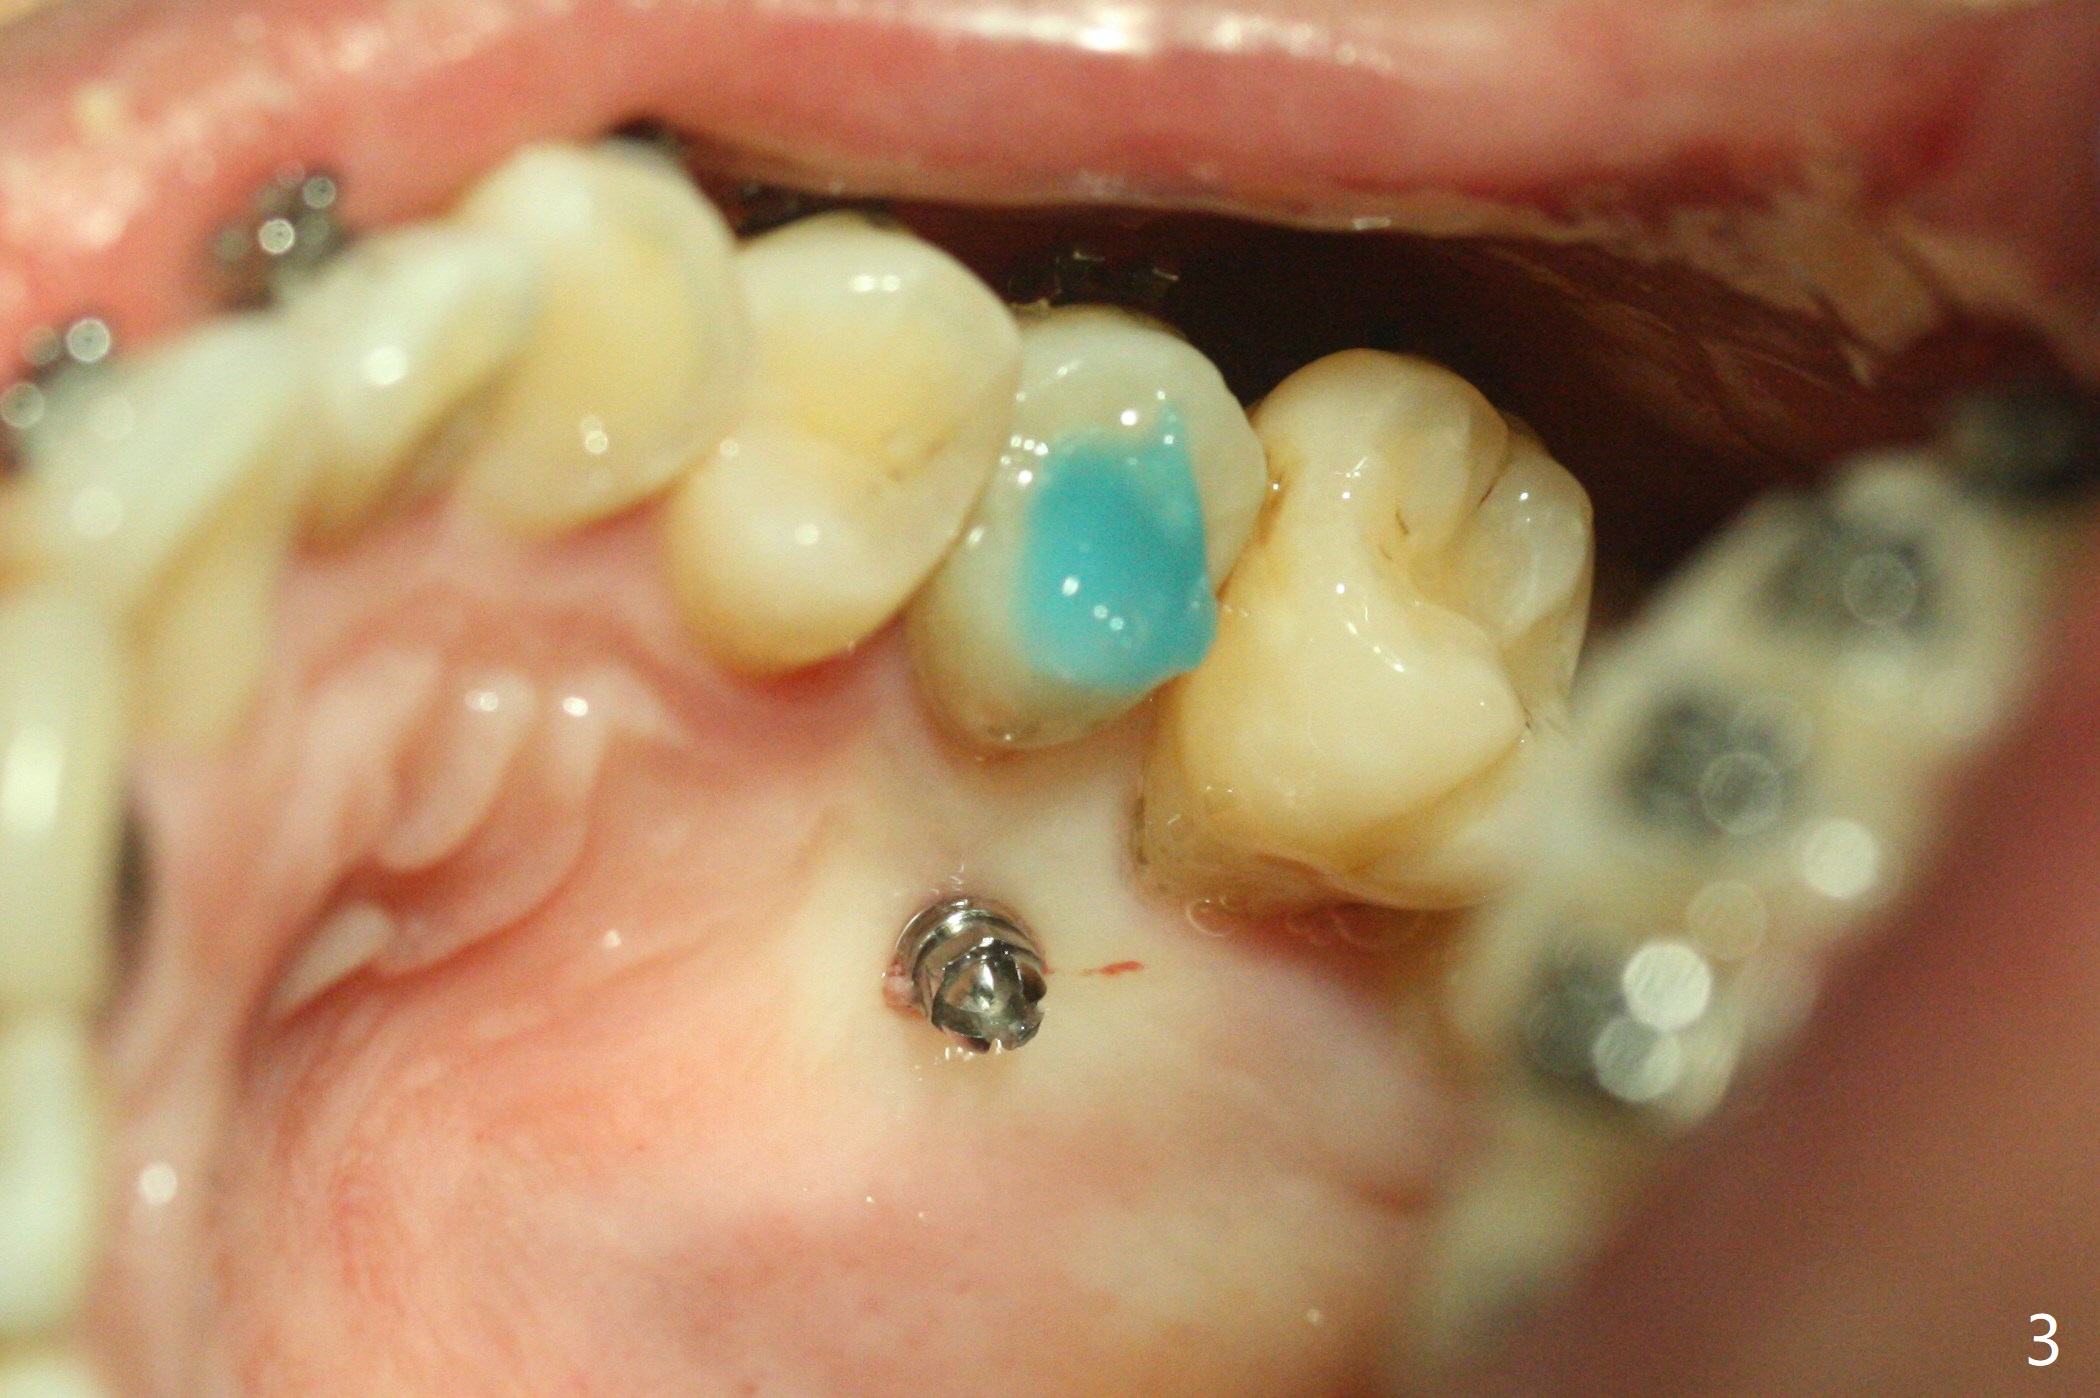

矫正器放置后一个月,正好有充裕时间,匆忙研究全景片(最好CT),好像左上6近中间隙大,近中颊侧,远中腭侧似乎是种植位点(图一:白圆圈),植入越高越宽,不容易伤及邻牙牙根。但是微型植体种植原则是必须种植在角化龈,减少炎症(以前不明白为什么)。当植体在移动牙龈植入时(图二:白箭头),牙龈浮起来,估计非角化牙龈也不能与植体产生紧密结合。取出后,完全可以在6近中颊侧角化龈植入,但是仔细检查发现远中颊侧角化龈更宽,所以在那里扎根(图二:黑箭头),因此腭侧就得选择近中(图三)。微型植体可以即刻使用,power chains常滑脱,压迫牙龈,在这个病例很可能进入远中牙间隙,所以需要在远中边缘嵴加树脂(图四,五:* (1.6x8mm))。第二天远中颊侧植体松动,取出后,插入2x10毫米一段式植体,仍然松动(图六)。CT显示植体下缘穿破牙槽骨(图七,骨质吸收严重与图八近中牙槽骨高度对比)。如果在近中颊侧重新植入微型植体,必须使用6毫米长植体(图九),所以最好在远中颊侧重新植入(图十:红色),缺损区(黑色)植骨。在使用14 niti时,左下7松动,病人同意拔除8,以后后推7,然后6种植(图十一:(左上8已拔除(x))),同时左上6远中植骨,左下8远中牙槽窝放置浸泡PRF液体胶原塞(图十二:1),近中牙槽窝粘性骨粉(2),最后牙槽窝上部PRF膜(3),PGA缝线。可能需要Cytoplast。